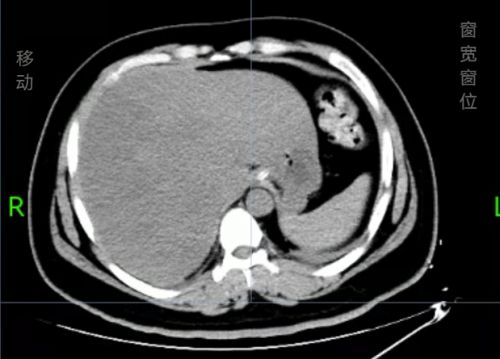

治疗后积气消失。

经过抢救病情好转,转出EICU。